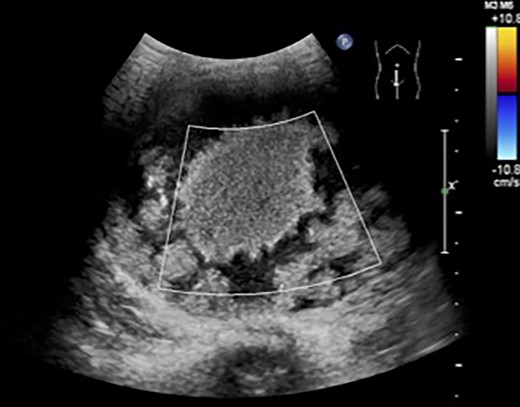

We diagnosed it as a wandering spleen with a giant SC and performed surgery. A small laparotomy was performed through an inverted Y-shaped incision of the navel, and a SC was found just below the wound. A partial biopsy of the cyst wall was performed, and a rapid pathological examination ruled out a malignant tumor. Aspiration of the cyst contents allowed the spleen to be externalized. Under direct vision, the blood vessels leading to the lower segment of the spleen were sealed, the splenic parenchyma was dissected by soft coagulation and a partial excision of the spleen was performed. The preserved upper pole of the spleen was put back into the abdominal cavity, and a pocket was made in the retroperitoneum under the left diaphragm using a laparoscopic method to store and fix the spleen (Fig. 4). Pathological examination revealed a pseudosplenic cyst covered with a hyalinized fibrous capsule. It was thought that chronic external force was applied to the migratory spleen and pseudocysts were formed. The postoperative course was uneventful and the patient was discharged from the hospital on the eighth postoperative day. At present, 3 years have passed, and the spleen has reached the same size as the ipsilateral kidney, and the cosmetic appearance is satisfactory.

(A) The spleen could be externalized by aspiration of the cyst contents through an umbilical incision. (B) A retroperitoneal pocket was created under the left diaphragm laparoscopically. (C, D) The superior pole of the spleen was placed in the retroperitoneal pocket and fixed.